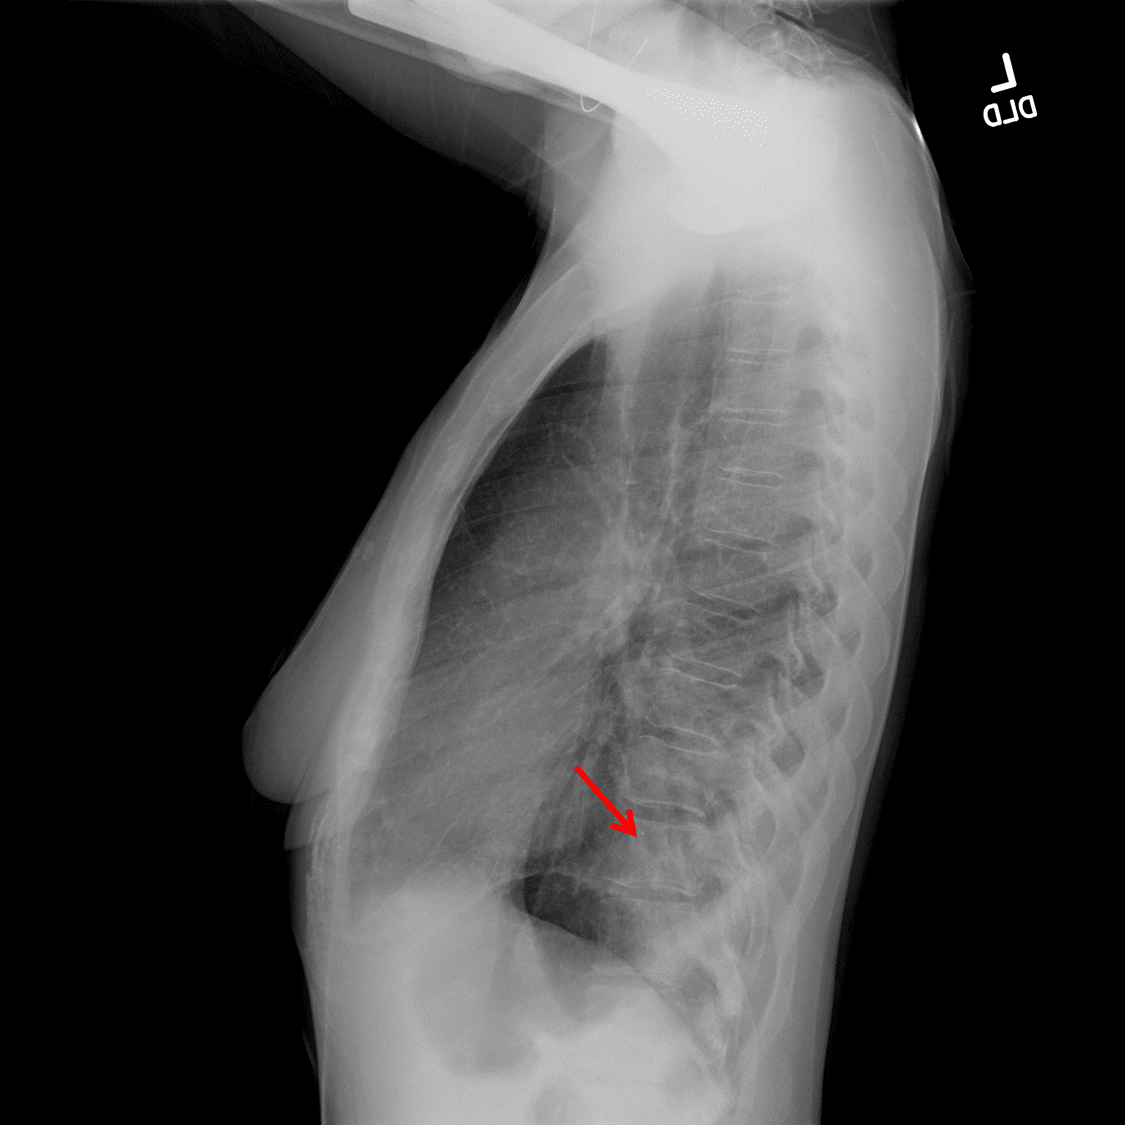

Sample ReportOpacification and volume loss in the left lower lobe consistent with lobar collapse. Intermixed bronchiectasis may relate to chronic infection or mucous plugging. Consider obtaining a chest CT to exclude a central obstructing mass.